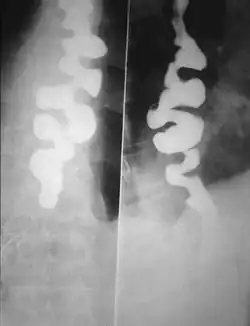

Rozlany skurcz przełyku – występowanie silnych skurczów mięśni przełyku. Występują one równocześnie na różnych poziomach, dając na zdjęciach rtg z kontrastem obraz przełyku korkociągowatego.

- Typowego obrazu radiologicznego – rtg przełyku po podaniu środka kontrastowego wykazuje upośledzony pasaż; wielopoziomowe skurcze mięśniówki przełyku dają obraz przełyku korkociągowatego. Silne skurcze mogą przypominać uchyłki.